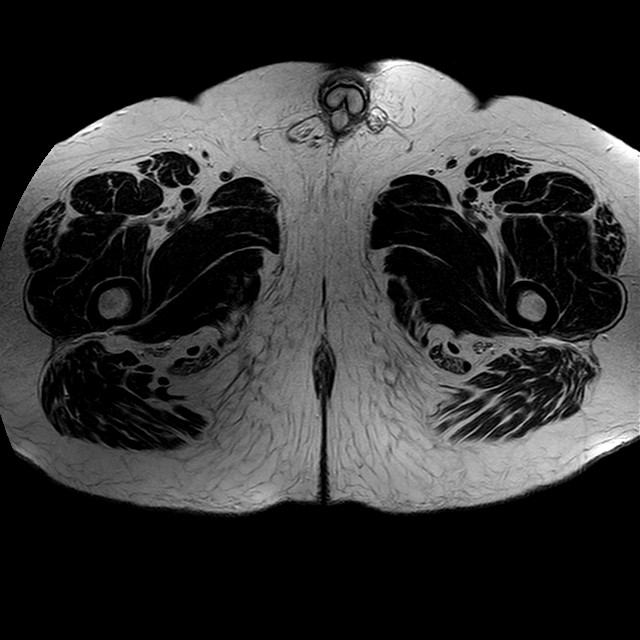

Esami: RMN BACINO

eT2w TSE

Evidenti e simmetriche alterazioni osteofitosiche in regione coxo femorale con riduzione delle rime articolari. Degenerazione completa del cercine glenoideo. Non attuali segni di versamento articolare. Non segni di edema osseo che escludono attuale algodistrofia od osteonecrosi. Lieve e simmetrica riduzione del trofismo della muscolatura glutea.